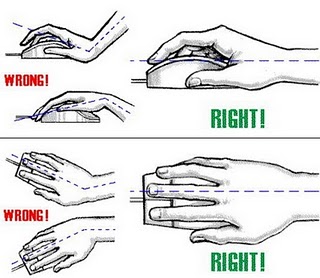

Uso correcto del Mouse y teclado...

¡Los errores del uso de el ratón a diario y el uso de teclado causarán el Síndrome de Túnel Carpiano! Use el ratón y el teclado correctamente. Vea debajo las fotografías tomadas en una cirugía de un paciente que sufre de Síndrome de Túnel Carpiano seguido de las TÉCNICAS CORRECTAS para uso....

Síndrome del túnel carpiano

Operación del tunel carpiano

El síndrome de túnel carpiano, es la presión sobre el nervio mediano, el nervio de la muñeca que proporciona sensibilidad y movimiento a partes de la mano. Esto puede ocasionar entumecimiento, hormigueo, debilidad o daño muscular en la mano y los dedos. El área en la muñeca por donde el nervio...